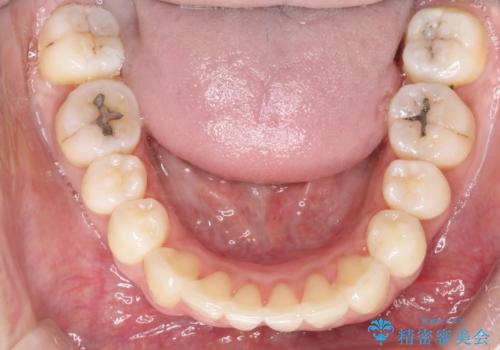

- リンガルブラケット

上顎の前から4番目の歯を両側抜歯して、上下裏側の装置で前歯を引っ込める計画としました。